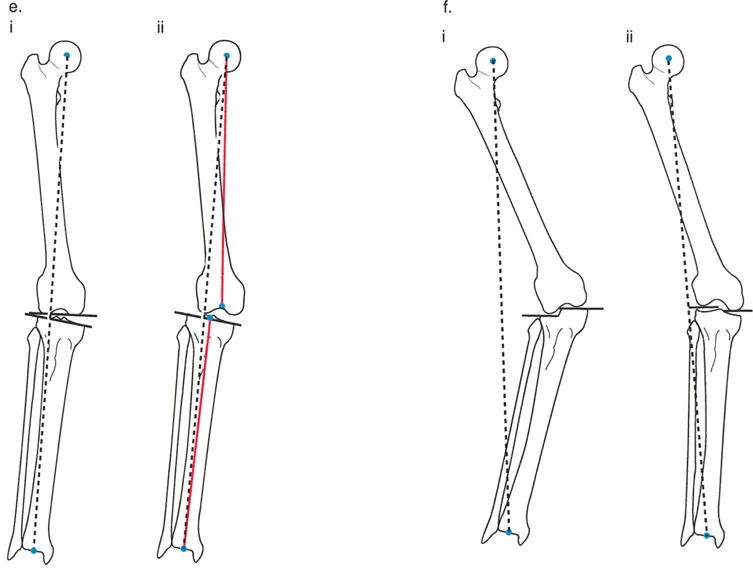

ماذا تعني الانحرافات؟

- التقوس (Varus Malalignment): إذا كان المحور الميكانيكي يمر بمسافة أكبر من الطبيعي إلى الجانب الإنسي (الداخلي) للركبة، فهذا يشير إلى وجود تقوس في الساق، حيث تبدو الركبتان متباعدتين والساقان مقوستين للخارج. هذا يزيد الضغط على الجزء الداخلي من الركبة.

- الفحج (Valgus Malalignment): إذا كان المحور الميكانيكي يمر إلى الجانب الوحشي (الخارجي) من مركز الركبة، فهذا يشير إلى وجود فحج، حيث تتجه الركبتان نحو بعضهما البعض (الركبتين المتلاصقتين). هذا يزيد الضغط على الجزء الخارجي من الركبة.

تعتبر هذه الانحرافات من أهم الأسباب المؤدية إلى خشونة المفاصل وتآكلها. الأستاذ الدكتور محمد هطيف يستخدم قياس MAD كأداة تشخيصية حاسمة لتحديد مدى الانحراف وتخطيط العلاج المناسب، سواء كان علاجاً تحفظياً أو جراحياً.

توجيه مفصل الركبة (المستوى الأمامي)

خط مفصل الركبة ليس عمودياً تماماً على المحور الميكانيكي للطرف السفلي. بل هو في الواقع مائل بحوالي 3 درجات فحج (valgus) بالنسبة للمحور الميكانيكي للفخذ، و3 درجات تقوس (varus) بالنسبة للمحور الميكانيكي للساق. هذا الانحراف البسيط هو تكيف بيوميكانيكي مذهل سنشرحه لاحقاً.

الزاوية الفخذية البعيدة الوحشية الميكانيكية (mLDFA)

هي الزاوية الوحشية (الخارجية) المتكونة بين المحور الميكانيكي لعظم الفخذ وخط مفصل الفخذ البعيد (خط مماس لأبعد نقطتين في لقمتي الفخذ الإنسية والوحشية).

* القيمة الطبيعية المقبولة لـ mLDFA هي 87.5 درجة ± 2 درجة.

* ملاحظة سريرية: عظم الفخذ البعيد يكون عادةً في درجة طفيفة من الفحج بالنسبة لمحوره الميكانيكي.

الزاوية الظنبوبية القريبة الإنسية الميكانيكية (MPTA)

هي الزاوية الإنسية (الداخلية) المتكونة بين المحور الميكانيكي لعظم الساق وخط مفصل الساق القريب (خط يمر عبر العظم تحت الغضروفي للسطح العلوي لعظم الساق).

* القيمة الطبيعية المقبولة لـ MPTA هي 87 درجة ± 2 درجة.

* ملاحظة سريرية: عظم الساق القريب يكون عادةً في درجة طفيفة من التقوس بالنسبة لمحوره الميكانيكي.